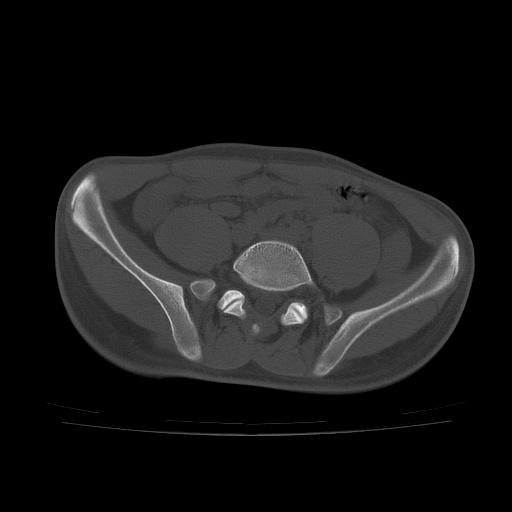

患者男性,18岁 腰腿痛1年  骶髂关节改变本人考虑强直性脊柱炎。

两侧骶髂关节骨质破坏,关节面毛糙,符合强直性脊柱炎骶髂关节改变。

两侧骶髂关节骨质破坏,关节面呈锯齿样改变关节间隙变窄,考虑强真性脊柱炎

两侧骶髂关节骨质破坏以髂骨为主,间隙变窄,强直性脊柱炎